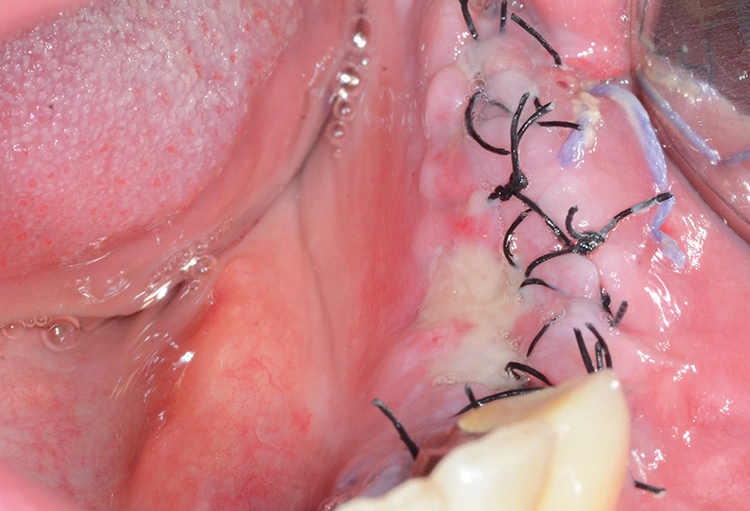

Augmentation

Tröltzsch

Tröltzsch Tröltzsch

Tröltzsch Tröltzsch

Tröltzsch Tröltzsch

Tröltzsch Tröltzsch

Tröltzsch Tröltzsch

Tröltzsch Tröltzsch

Tröltzsch Tröltzsch

Tröltzsch Tröltzsch

Tröltzsch